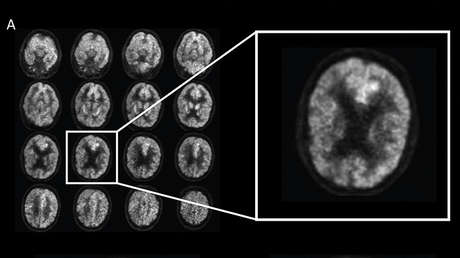

El mal de Alzheimer está marcado por el deterioro de la memoria y la confusión. Fisiológicamente, una sustancia llamada beta amiloide se acumula en los cerebros de los enfermos. Estas son las placas que interfieren en la función de las células cerebrales. La señal clásica de la enfermedad. Los científicos también han observado que los enfermos de alzhéimer pierden masa cerebral y estiman que la inflamación crónica puede contribuir al desarrollo de la demencia.

De acuerdo con el estudio presentado el martes pasado en la conferencia de la Sociedad para la Neurociencia, los resultados del experimento demuestran que los roedores tratados con THC vieron una reducción significativa en el tamaño de las placas cerebrales asociadas con la enfermedad.

Además, los cerebros de estos ratones tenían un 20 % menos de placas beta amiloides y presentaban menores signos de daño por inflamación. También obtuvieron mejores resultados en las pruebas relacionadas con sus recuerdos.